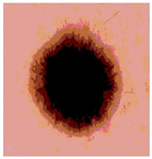

![]() | ![]() | ![]() | ![]() |

| Img1 | --- Pixel Intensity (0–255) ---> | ||

| Img2 | --- Pixel Intensity (0–255) ---> | ||

| Img3 | --- Pixel Intensity (0–255) ---> | ||

| Img4 | --- Pixel Intensity (0–255) ---> | ||

| Img5 | --- Pixel Intensity (0–255) ---> | ||

| Img6 | --- Pixel Intensity (0–255) ---> | ||

| Img7 | --- Pixel Intensity (0–255) ---> | ||

| Img8 | --- Pixel Intensity (0–255) ---> | ||

| Img9 | --- Pixel Intensity (0–255) ---> | ||

| Img10 | --- Pixel Intensity (0–255) ---> | ||